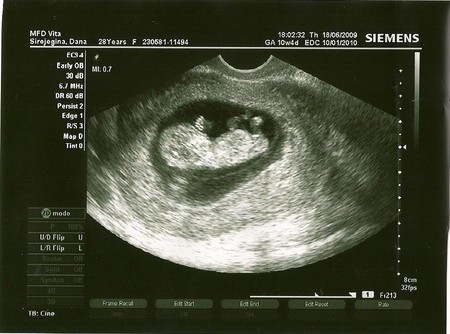

11-ая неделя...узи ;-)

Сегодня была на приёми,делали узи со всеми замера.по научному наверное называется скрининг.У нас всё в норме,малыш догнал по размерам свой акушерский срок-10 недель и 5 дней.После всех замеров , медсестра позвала Полинку в кабинет,посмотреть на малыша.Мой старший ребёнок был в шоке)))))особенно от того,что когда она подошла к монитору,мой младший ребёнок,повернулся к ней и помохал ручкой))))Поля до сих пор не может успокоиться-МАМА МАЛЫШ МЕНЯ УВИДЕЛ И ПОМАХАЛ!!!!!

И не говори,я как бы уже типо опытная)))но вчера опять была в шоке....только три недельки назад,там был малышок похож на большое зёрнышко боба))))а вчера....руки ноги,всё в движение,мозг такой красивый))))медсетра сказала-футболист))))я сказала-учёный))))а Полинка молча стояла и не моргала)))))

Девочки,я тоже думала.вернее была уверенна,что будут по живуту,ан нет,делали вагинальное!!!!Врач просто изначально,до узи сомневалась,будут ли делать сегодня замеры,просто 3 недели назад,малышонок был ещё маловат и немного отстовал от срока.А в этот раз он догнал))))и можно было всё замерить и написать в карту.Я думаю,что это не панацея, и многим делают узи на таком сроке по животу.НО мне вчера делали вагинальное,обосновываея это тем,что так лучше видно на моём сроке!